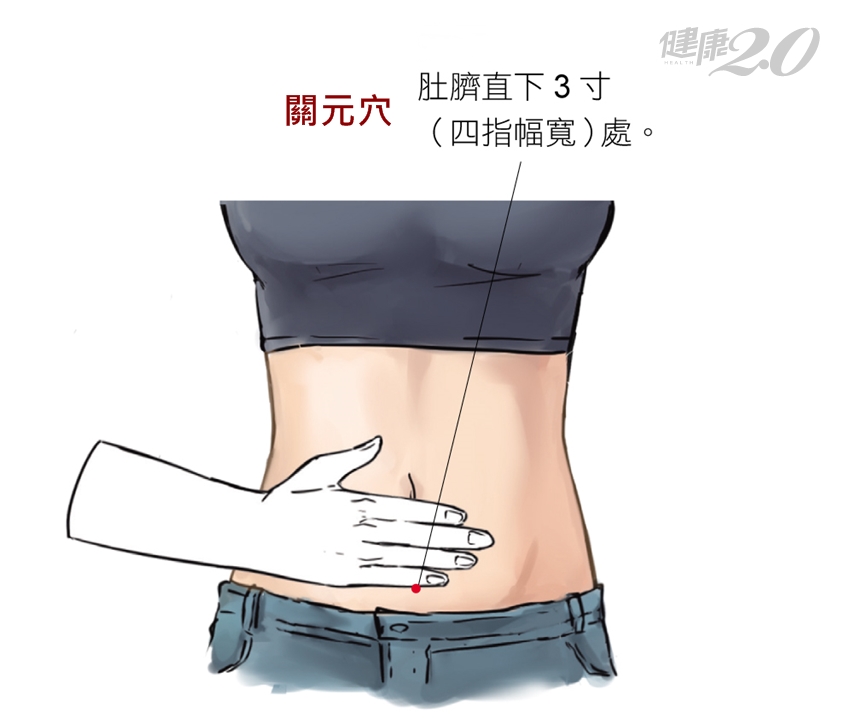

關元穴 改善四肢冰冷

關元穴隸屬於任脈,而任脈,是奇經八脈之一。依據《素問.骨空論》記載:「任脈者,起於中極之下,以上毛際,循腹裡,上關元,至咽喉,上頤,循面入目。」任脈與六陰經脈都有聯繫,稱為「陰脈之海」,具有調節全身陰經氣血的作用,共有24個穴位。關元穴位於下腹部,前正中線上,位於肚臍下三寸,具有溫腎益精、回陽補氣、調理沖任、理氣除寒作用。

臨床上,關元穴可以用來治療陽痿,以及早洩、月經不調、子宮功能性出血、帶下、不孕、子宮脫垂、全身衰弱等症狀,也可以調理腹瀉、腹痛、痢疾、小便不利(小便量減少、排尿困難或小便完全閉塞不通)、尿道感染。此外,本穴為保健要穴,有強壯作用,按摩此穴位,亦可治療下焦虛寒的問題。